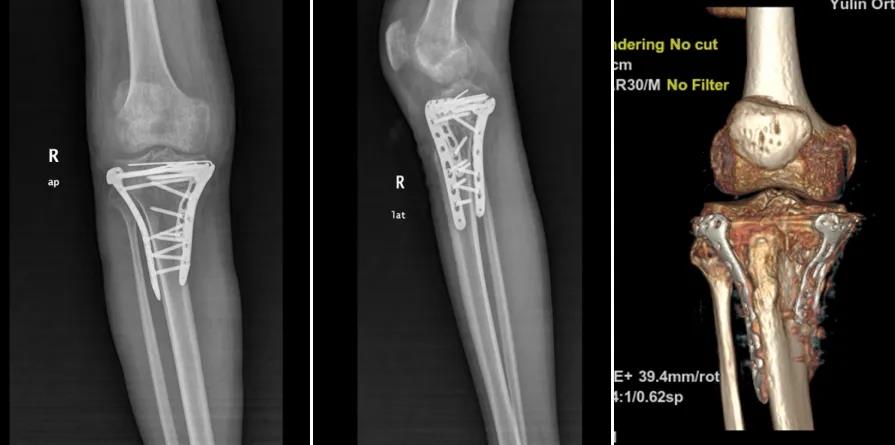

依托这具高仿真模型,经科内严密讨论,反复推敲,最终确定了“膝内侧、外侧入路三钢板固定+植骨”的精密手术方案。这一清晰的规划,瞬间驱散了罗某心中积压已久的阴霾,使其重燃站立希望。

手术当日,作为主刀的朱博副主任医师,凭借精细入微的操作和手术团队的高效协作,这台被视为“极高难度”的手术一气呵成,仅历时两小时便顺利完成。术后,朱博副主任及主管卜庭用医师对罗某的康复极为重视,亲自指导其进行系统性的膝关节功能康复训练。

在科室医护人员的精心治疗与照护下,罗某恢复迅速:复查片显示骨折对位对线良好,关节面平整,膝关节疼痛显著缓解,关节活动度大幅改善。久违的笑容终于回到他的脸上:“是玉林市中西医结合骨科医院的专家们,给了我重新站起来的机会!手术技术太强了,感谢朱主任、卜医生和所有医护人员!”

朱博副主任感言:罗先生的病例极具挑战性,胫骨平台粉碎性骨折,属Schatzker Ⅴ型,过伸内翻型胫骨平台双髁骨折,即使新鲜骨折手术难度就较大,加之外伤后3个多月,骨折已畸形愈合,手术难上加难。是三维CT及3D打印技术带来的‘术前透视’能力与团队多年积累的临床经验相结合,才创造了这次成功。我们将持续探索创新技术应用,以更精准、更微创、更高效的方式,守护每一位骨伤患者重新站立的权利。